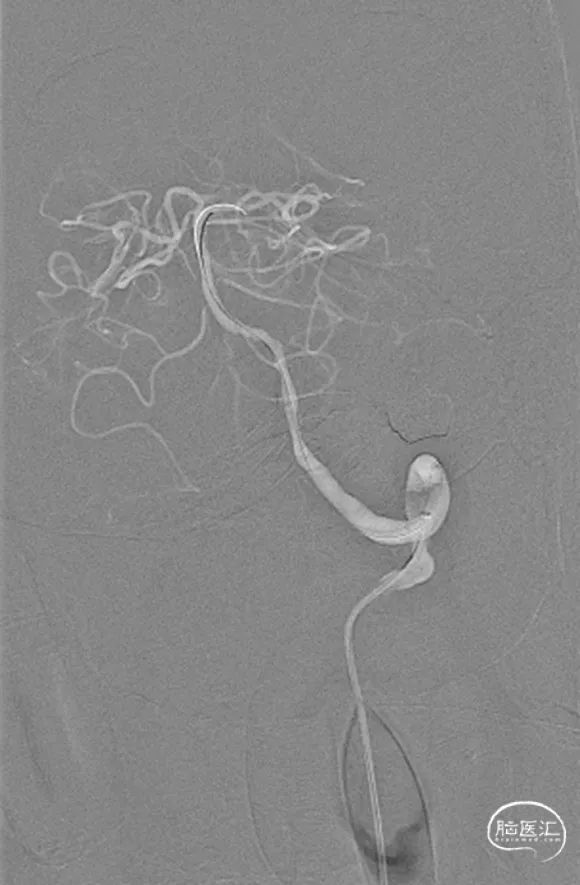

术前造影

术后造影